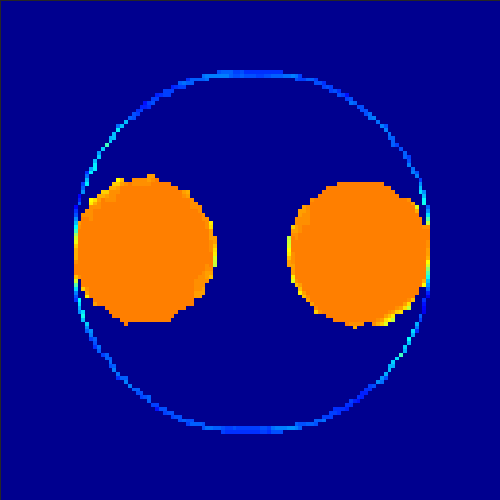

5.2 Monte Carlo Simulation

In order to test the behaviour of the proposed method in a more realistic, random-based test case, we performed a Monte Carlo simulation for dynamic SPECT imaging. First, we created a simple image phantom consisting of an outer and two inner circles which represents the structure of the region of interest (see figure 8(a)). Within those regions we assumed concentration curves over a time period of 90 time steps as displayed in figure 8(b). Based on the tracer intensity in an image frame at each time step, we created a variable number of random decay events (where the number is proportional to the average concentration in one pixel in the whole image frame per time step) with a probability proportional to the concentration in every subregion. They are detected by a virtual double head gamma camera rotating around the patient by 46 degrees per time step, which consists of 374 detector bins. Every simulated decay event is projected onto the scanner and counted by the corresponding detector bin.

In two different tests we fixed the number of events counted by the detector equal to (resp. ) times the average concentration in one pixel. The resulting sinogram images of the accumulated counts in each bin are shown in figure 9.

Based on the sinogram data we applied the proposed algorithm in order to reconstruct the original image sequence. The results for both test cases are shown in figure 10.

As one can see, the method is able to reconstruct the regions properly, even in case of a low count number. Within a number of iterations (average of 100 outer and 10000 inner iterations), the algorithm presents a reasonable reconstruction of the region of interest and the corresponding regional tracer concentration curves. Here, the parameters were not optimized as in the case of the synthesized data sets in the previous section, but kept fixed as , and . With futher optimized parameter values one could possibly provide even better results.